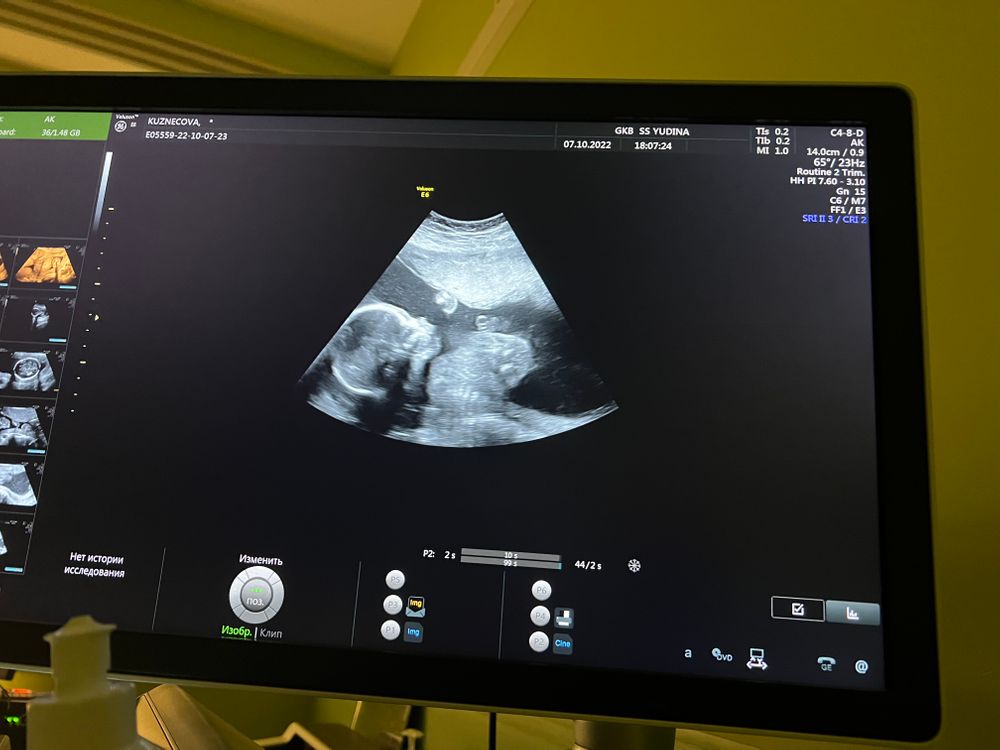

Мой 2 скрининг, 20 недель, ПОЛ, фотопуз✨

Узи делают, смотрю 6а монитор. Отчётливо вижу девочку. Врач,, вам сказать или написать на бумажке пол? ". Я говорю, что хорошо видно девочку... Поздравляю) я тоже больше за девочку была.